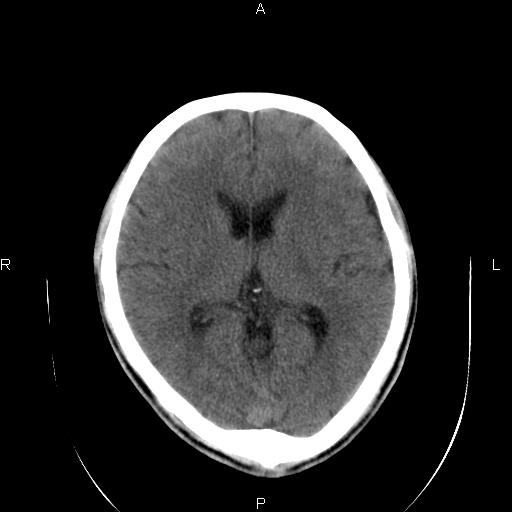

男性,40岁,反复头痛,视物旋转一月余,无呕吐,pe未见明确异常。

我的问题是上矢状窦高密度怎么解释?请各位专家不吝指教,谢谢!

可结合增强或mrv检查除外上矢状窦血栓。

颅脑ct轴位平扫颅内未见明确异常;建议必要时行mri检查。